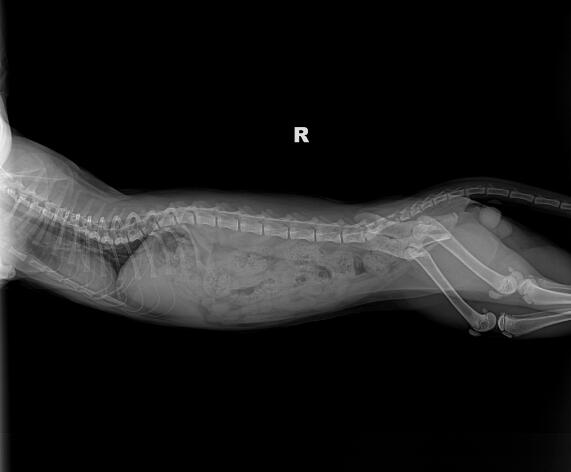

所有的猜测都还是要经过专业的诊断的,在怀疑自己的矮脚猫有胸腔狭窄的情况,那么就可以去宠物医院给它做一个检查,跟医生讲出自己的怀疑,通常时候宠物医生见多识广,一眼就能判断个七七八八的,剩下的就是专业设备的检测,做一个心脏彩超就能完全确定了。